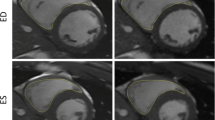

Cine images were slightly superior to RT images in most structural visualization categories, especially in patients with good breath hold (Table 3 and supporting video in Online Supplementary Material 1, Part 1). Minor differences were seen in LV/RV endocardial borders (cine: 3.7 ± 0.4; RT: 3.5 ± 0.5), epicardial borders (cine: 3.7 + /0.4; RT: 3.5 ± 0.5) and myocardium (cine: 3.8 ± 0.3; RT: 3.6 ± 0.5). Cardiac motion showed no difference between both techniques (cine: 3.9 ± 0.2; RT: 3.9 ± 0.2). Whereas especially the visualization of the papillary muscles (cine: 3.9 0.2; RT: 3.5 ± 0.5) and the blood pool contrast (cine: 3.9 ± 0.3; RT: 3.5 ± 0.5) showed better visualization on the cine images. Wilcoxon sum rank test proved the differences in the visualization of the papillary muscles and the blood pool contrast statistically significant (papillary muscles: P < 0.01; blood pool contrast: P = 0.02). RT-MRI was superior in image quality, especially in young patients with breath holding problems (Fig. 3 and supporting video in Online Supplementary Material 1, Part 2).

Representative images of the youngest patient, a 5-year-old girl (patient 19) falling asleep during RT-MRI. Images in short axis orientation from basal (plane 8), mid-ventricular (plane 11) and apical (plane 15) levels are presented at end-diastole and end-systole for RT-MRI (RT balanced SSFP sequence) and corresponding cine MRI (conventional cine balanced SSFP sequence). RT-MRI showed excellent image quality. In contrast, cine MRI suffered from respiratory ghosting. Arrows mark respiratory artifacts. MRI magnetic resonance imaging, RT-MRI real-time magnetic resonance imaging, SSFP steady-state free precession

While cine images, especially in younger patients often showed respiratory artifacts on multiple slices (1.5 ± 1.4), respiratory artifacts did not occur in RT-MRI (0.0 ± 0.0). Wilcoxon rank sum test proved the increased incidence of respiratory ghosting on cine MRI statistically significant (P < 0.01).

At present, cine MRI with slice per slice data acquisition and repetitive breath holding is the clinical standard for the examination of cardiac volumetry. In cases where breath holding is impossible due to preexisting conditions or patient age, cine MR images may be acquired during free breathing, which is associated with significantly poorer image quality. For patients with heart or lung diseases, and especially for children, breath holding is a major disadvantage that reduces the patient’s comfort [5], induces additional anxiety [22] and is unreliable for small children and infants. RT-MRI enables image acquisition during free breathing with simultaneous high image quality. The fact that the youngest participant in the study fell asleep during RT-MRI emphasizes the great advantages of free breathing. This indicates that cardiac volumetry based on RT-MRI is likely suitable for sleep and feeding methods in neonates and infants as established for other applications such as brain MRI [23] or for cardiac MRI and flow measurements that do not require breath holding [24, 25]. Potentially eliminating sedation or general anesthesia could reduce the resources needed for imaging and would offer major patient safety benefits, as both pose short- and long-term risks [26]. In addition, general anesthesia and sedation impair cardiac function. Anesthesia with mechanical ventilation based on positive intrathoracic pressure completely reverses the physiological respiratory influence on cardiac function [27].

In our study, problems with breath holding often resulted in respiratory ghosting on cine images, reducing image quality. This has been demonstrated in previous studies [13]. In our study cine MRI was slightly superior in structure visualization in adolescent patients, RT-MRI acquired during free breathing achieved better ratings for the structure visualization in younger children with breath-holding problems.